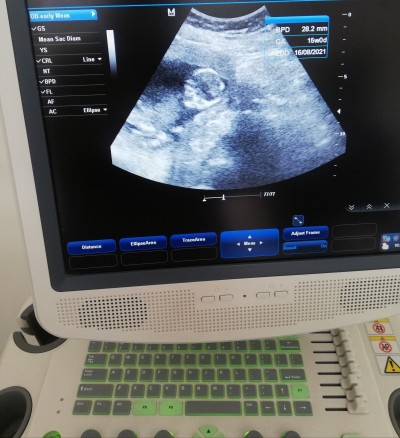

Ultrason görüntü

fanlayan var mı doktor cinsiyet için bişey demedi

14.5

Birşey belli olmuyor cnm.Sordun mu peki doktora.Gonlunden ne geçiyorsa o olsun inşallah

Sordum erken dedi canım birazda zor belli olur dedi kilodan

Aynen dediği doğrudur cnm ilerleyen haftalar da öğrenirsin inşallah sağlıklı olsun da

Görüntü bile zayıf sanki

Burada dizlerinin uzerine oturur gibi onden cekmis doktorrr gozuken bisey yokkk csnim